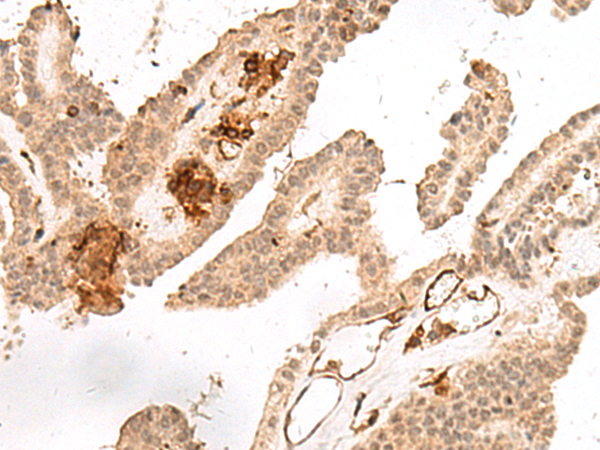

分类: 科研抗体货号: P13443别名:应用: WB,IHC反应种属: Human